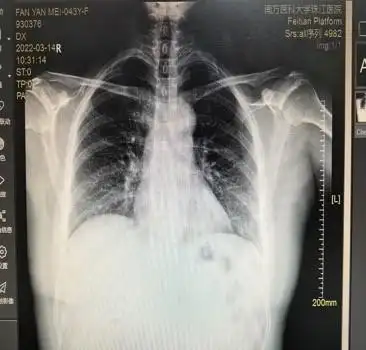

医学影像学-循环系统实习 心脏形态异常-普大型心脏 心脏向两侧均匀

同时,心脏两侧均匀增大,故诊断为普大型心脏,常见于心脏衰竭,大量心包

心脏增大二尖瓣型主动脉型普大型后前位正常心脏示意图如图3226